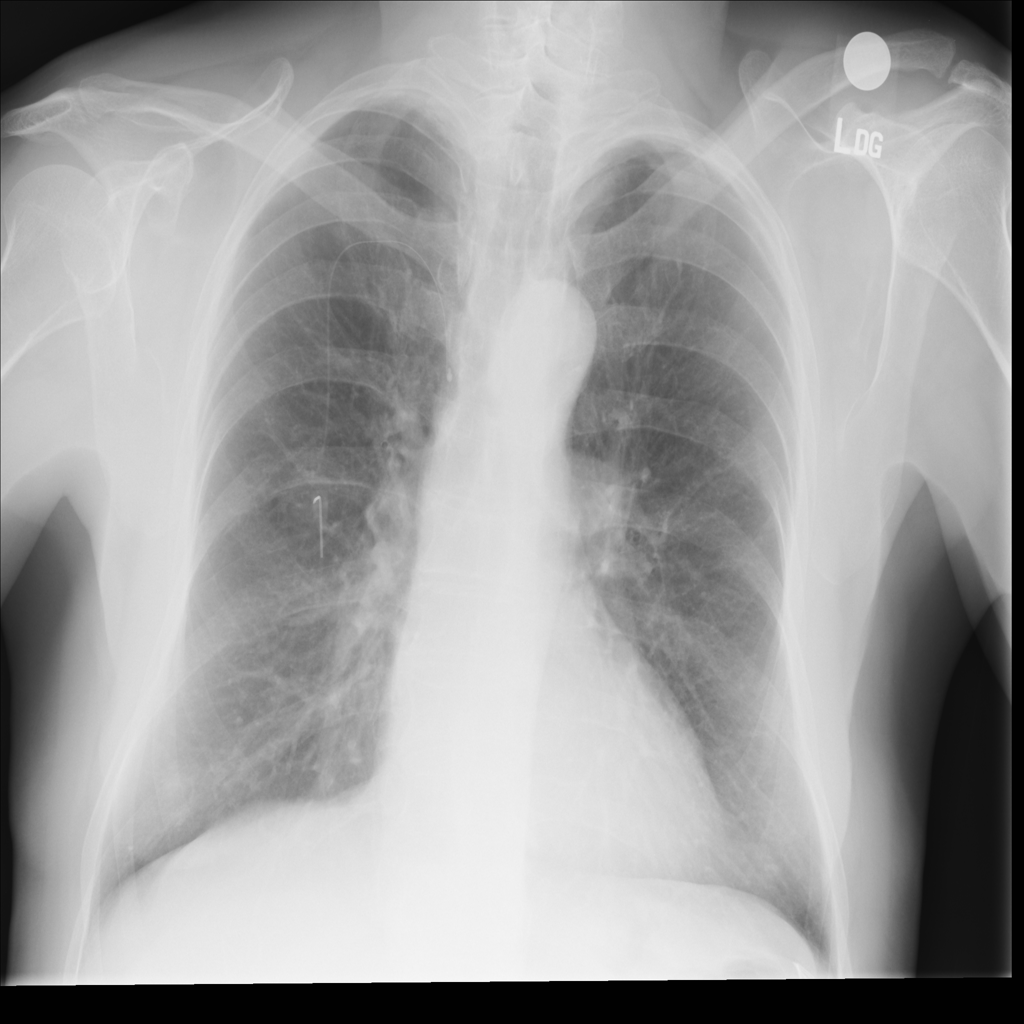

PAT-894B · IMG-000Emphysema

PAT-894B · IMG-000

PA